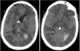

Diffuse cerebral edema